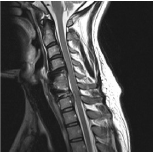

MRI revealed disc herniation at C6-C7 sequestrated to below C7 vertebral body (Figure 2), and no abnormal findings in thoracic spine. We suspected that cervical disc herniation was responsibility lesion of anterior chest and back pain.

Figure 2. Preoperative T2-weighted sagittal MRI demonstrating large disc herniation at C6-C7 level.